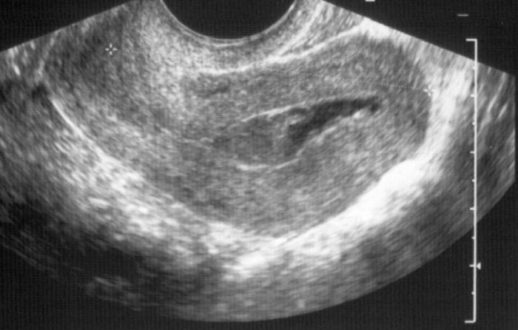

Сразу при обнаружении замершей беременности вам предстоят обследования, которые будут проведены в любом случае и уже могут дать полезную информацию: трансвагинальное УЗИ позволяет исключить такие причины как опухоли матки, её пороки развития.